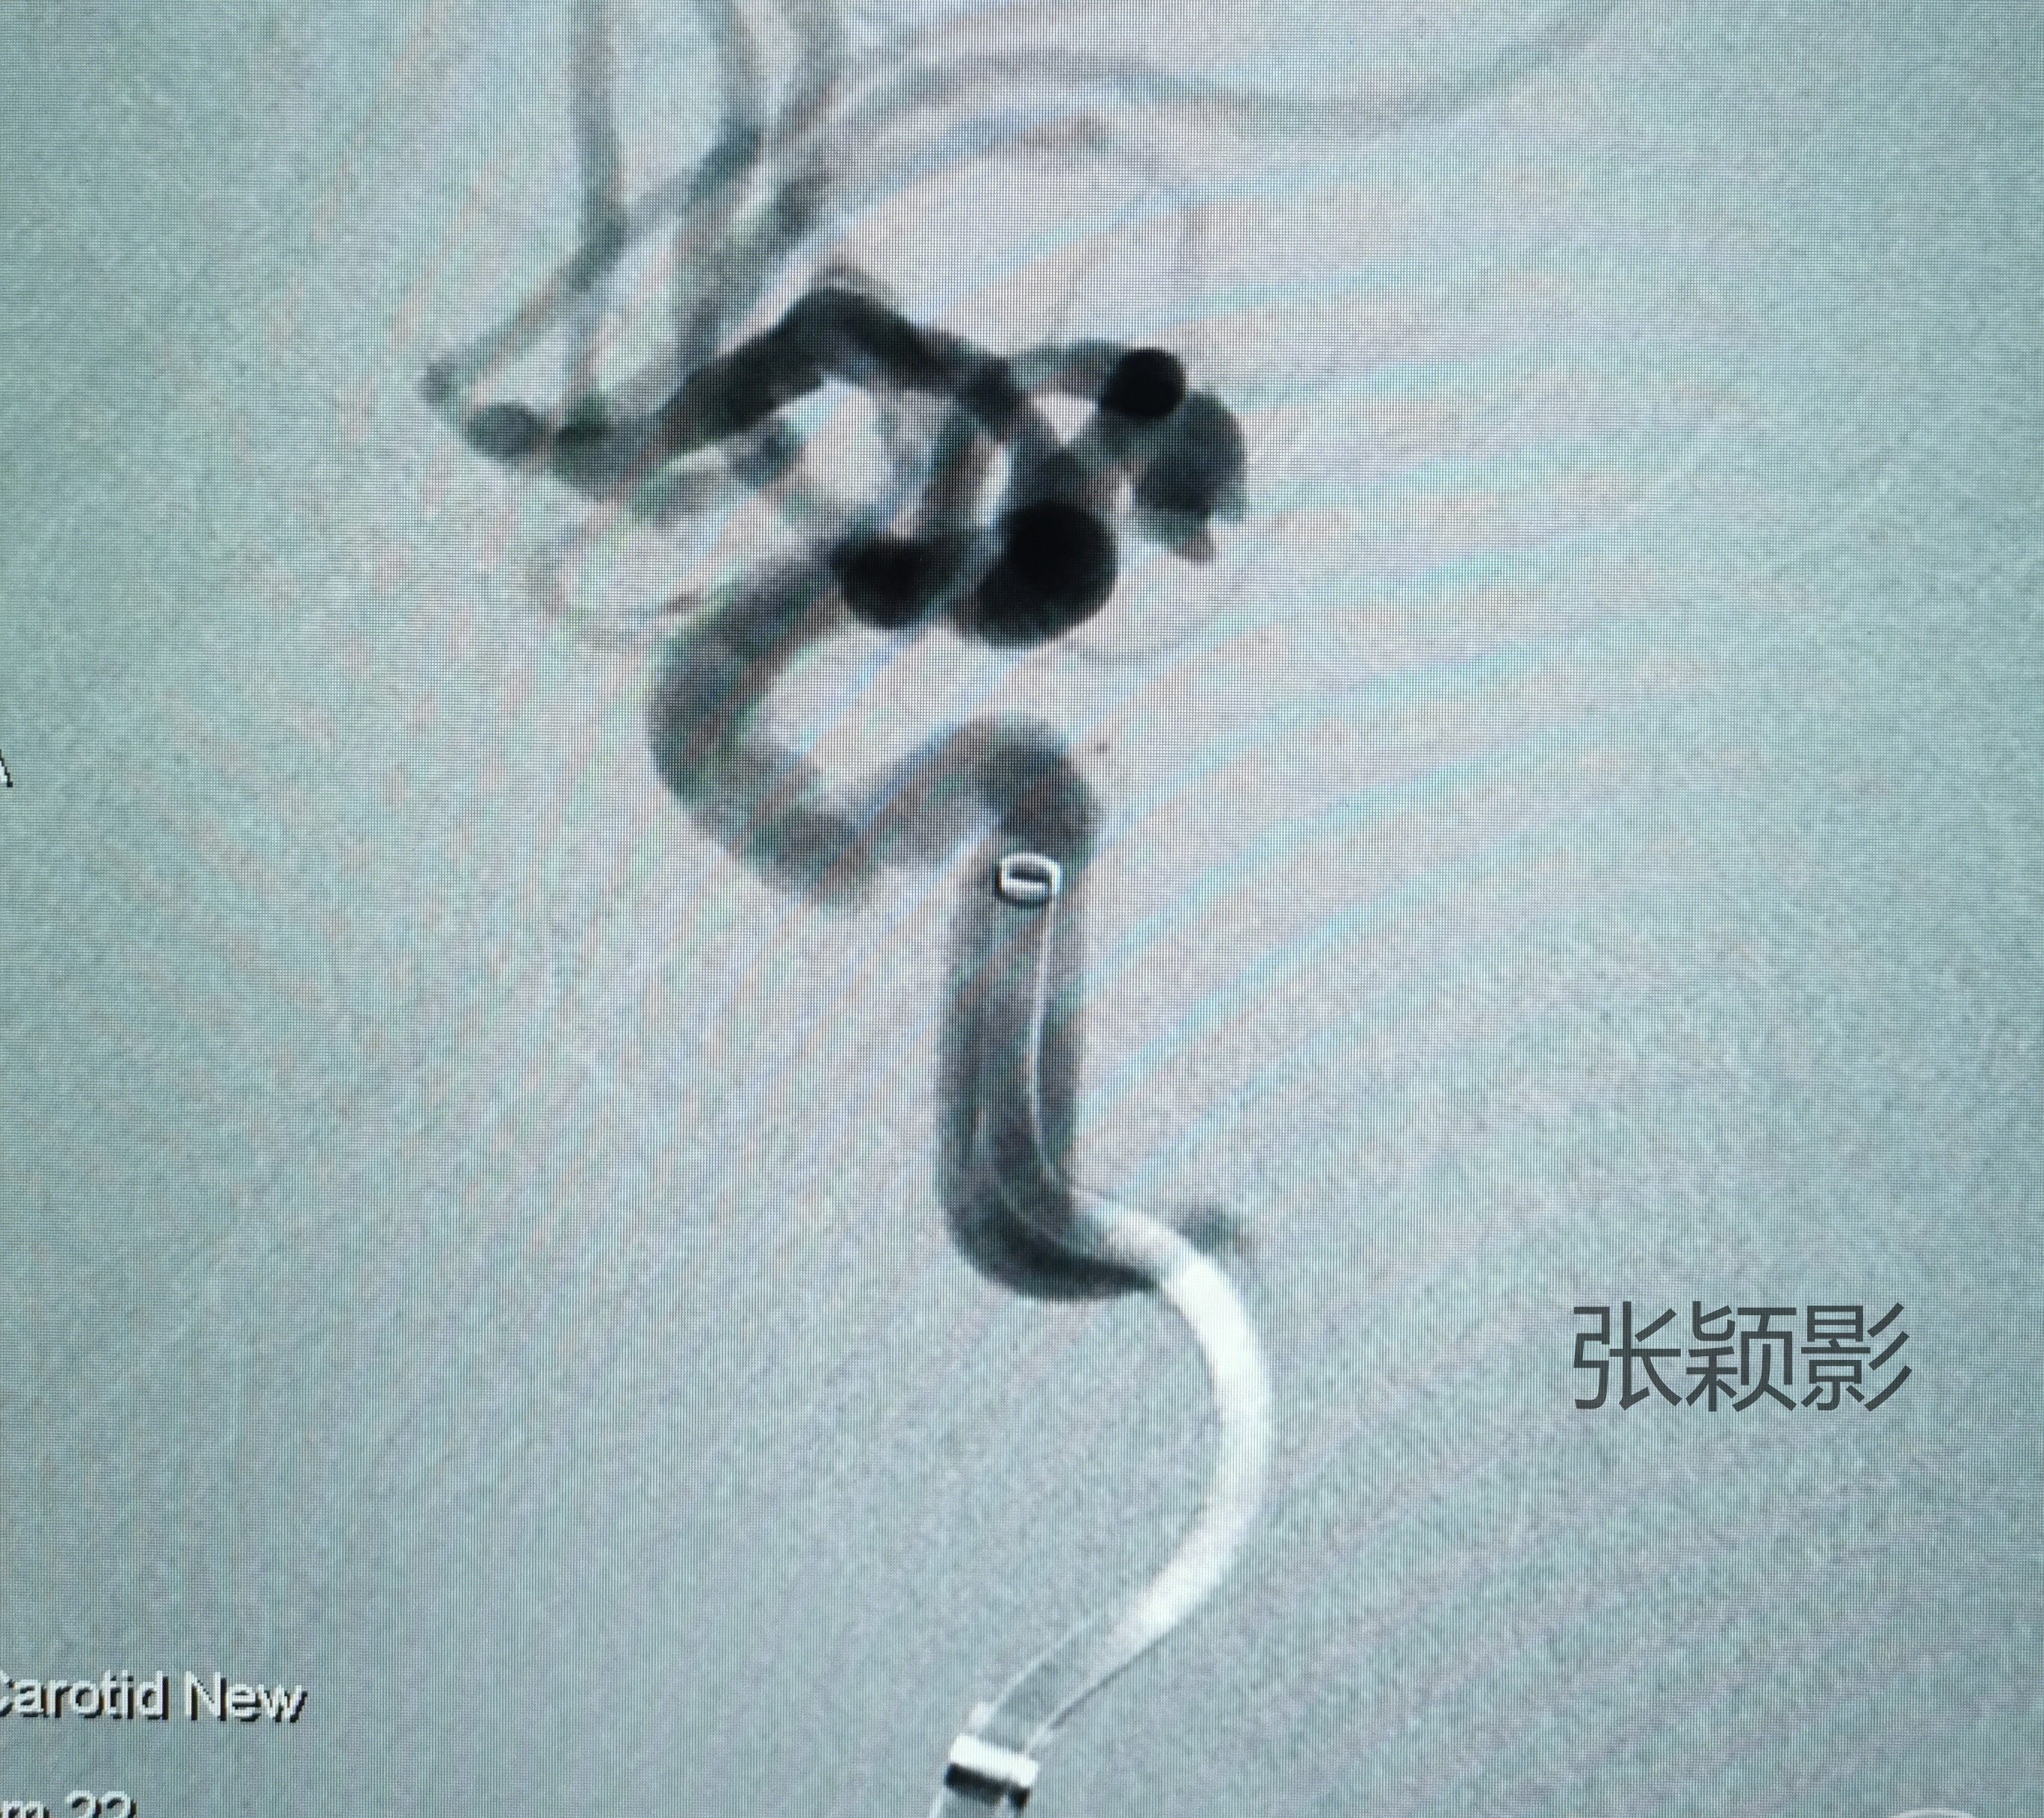

旋转重建图像可以比较全面的展示动脉瘤的不规则形态。不得不说,治疗A1段动脉瘤时会特别羡慕有双C的同道们......

由于动脉瘤相对宽颈,还是计划准备支架辅助栓塞,如果能够单纯栓塞解决,那不放支架也妥。支架微导管顺利到位后开始进行动脉瘤超选,准确塑形后,弹簧圈微导管非常听话自动到位🤩。